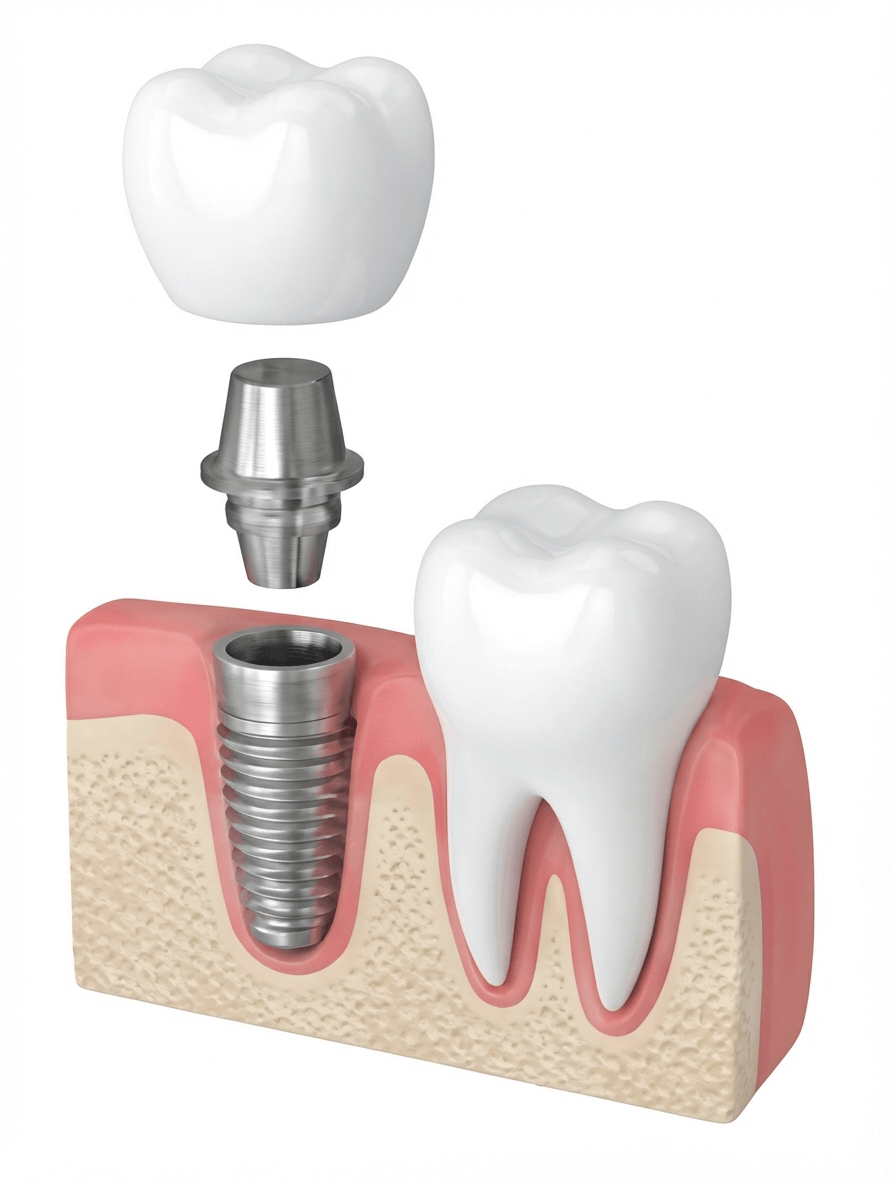

インプラントとは?

インプラント治療とは、失った歯を取り戻すための最新の治療方法です。

歯を失った部分の顎の骨に、チタン製の人工歯根(インプラント体)を埋め込み、その上に人工の歯を装着することで、天然の歯とほぼ同じ機能と見た目を回復できます。

一次手術(インプラント埋入)

二次手術(アバットメント装着)

人工歯の製作・装着